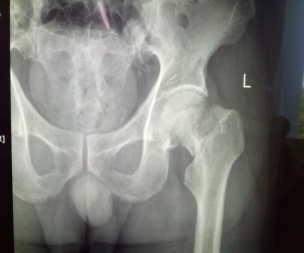

患者張XX,男,75歲,6月前腦梗塞遺留左側(cè)肢體偏癱,合并高血壓、糖尿病。